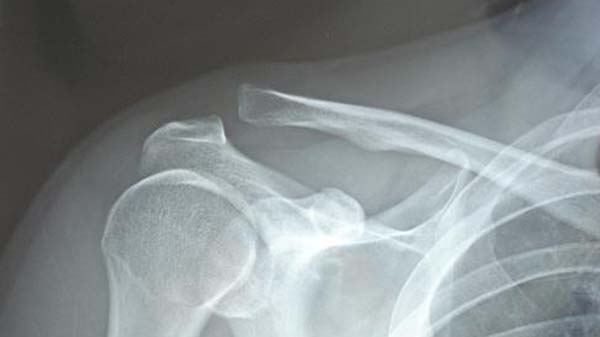

*赤丸肩鎖関節です

コンタクトスポーツや転倒で肩の側面をぶつけてしまった場合、その衝撃が鎖骨を外側にある肩鎖関節に加わり、靭帯損傷を起こし鎖骨と肩峰(肩甲骨の一部)の位置異常を起こし肩鎖関節脱臼が起こります。

1.鎖骨の外の端が盛り上がったようになっているのも、肩鎖関節脱臼の特徴です。